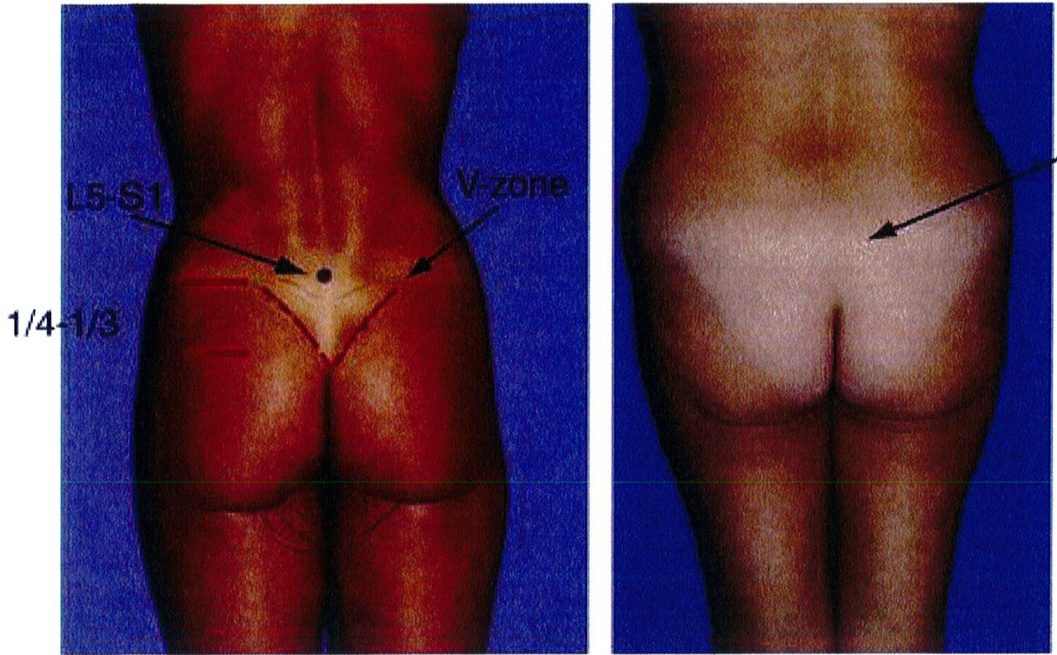

Về lý thuyết, khoang cùng sẽ được định nghĩa là vùng nằm giữa khe gian đốt L5-S1 với điểm trên cùng của đường liên mông; chúng sẽ bằng khoảng 50% – 100% chiều dài nếp liên mông. Ở Hình 14, chiều dài nếp liên mông được coi là lý tưởng khi chúng bằng một nửa chiều cao cơ mông lớn, với ¼ đến 1/3 khối mông nằm trên đường tiếp tuyến với điểm cao nhất nếp liên mông, và ¼ đến 1/3 khối mông nằm dưới đường tiếp tuyến với điểm thấp nhất của nếp liên mông. Điểm dưới cùng này chính là giao thoa của nếp lằn mông hai bên. ở những bệnh nhân có khung hình V, chiều cao của cơ mông thường ngang bằng với đường liên mông ngắn, tạo ra ảo giác rằng nửa trên của cơ mông bị mất đi/không có (Hình 14).

Bởi trên cùng của cơ mông phải vượt qua khoảng ¼ đến 1/ 3 đường cong tính từ vị trí điểm cao nhất của đường liên mông. Nếu bờ cơ mông hoặc vùng V không được xác định rõ, mông trông sẽ bị dẹt, không căng tròn. Để cải thiện vùng V, hãy đánh giá xem vấn đề dẹt là do thừa mỡ hay thiếu thể tích mông, hoặc cả hai. Để từ đó quyết định xem nên hút mỡ hay nâng mông bằng implant hoặc ghép mô mỡ, hoặc cả hai.

Trong vùng mông trên, phần tiếp giáp giữa đường liên mông và tam giác cùng phải là một hình chữ V lõm sâu vào trong. Vùng này được gọi là vùng chữ V.

Để mô tả khối cơ mông trong mối tương quan giữa nếp lằn mông và đùi, hãy lấy đường liên mông làm trung tâm. Đầu trên của đường liên mông có thể xác định một cách rõ ràng; tuy nhiên, đầu dưới thì không dễ dàng như vậy. Điểm dưới cùng này là nơi mà hai bên mông tách ra từ đường giữa. Nếu lý tưởng thì điểm dưới này phải nằm ở 2/3 dưới hoặc ¾ dưới của chiều cao khối cơ (Hình 22). Hai mông tiếp tục tách về hai phía cho tới khi chúng gặp ‘khớp nối’ vùng đùi trong. Tại vị trí này, nếp lằn mông hợp với đường liên mông góc 45°.

Vùng này lõm vào bao nhiêu sẽ ảnh hưởng tích cực đến tính thẩm mỹ bấy nhiêu. Nếu lý tưởng, bờ các khối cơ mông phải dễ dàng xác định được bằng cách sờ ở phía bên ngoài, với hình dạng bán nguyệt cong lên trên (Hình 21).

Muscle edge is not defined

Hình. 21. Đánh giá mối tương quan giữa cơ mông và vùng trên trong mông và tam giác cùng. Ở ảnh bên trái, điểm chấm đen là khớp gian đốt L5-S1, đường nét liền phía dưới đành dấu điểm cuối cùng của đường liên mông, và đường chấm đánh dấu điểm cuối cùng của bờ trên cơ mông lớn. Bệnh nhân ở phía bên trái có thể thấy rõ vùng chữ V cũng như bờ cơ mông lớn. Bệnh nhân bên phải không thấy vùng chữ V vì thiếu thể tích vùng mông cũng như thừa mỡ vùng V, vì thế trông mông sẽ bị det.